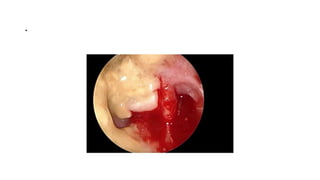

Bulbar Transconjuctival Orbitotomy

• .

Bulbar conjunctival incision

Bulbar transconjuctival incision

Cavernous Hemangioma